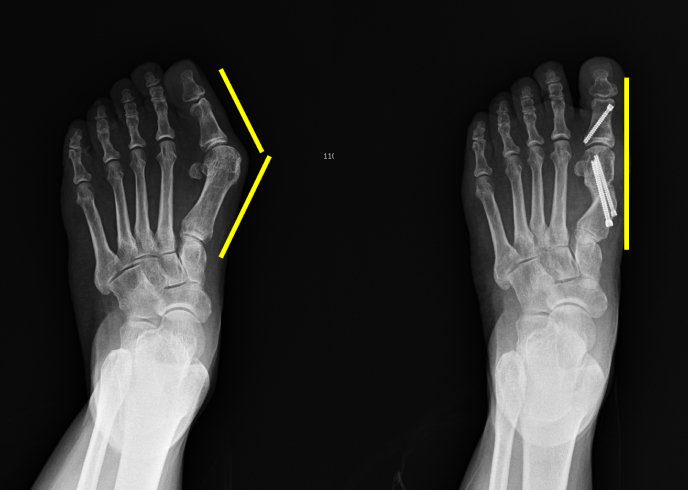

A+ 4세대 최소 흉터 무지외반증 수술

A+ 4세대 최소 흉터

무지외반증 수술은

2~3mm 절개로 뼈 교정,

통증은 줄이고 흉터는 거의 없습니다.

A+MITA(Minimal Invasive Transverse Akin)

수술은

엄지발가락 휘어짐을 교정하는

최소침습 수술법입니다.

2~3mm 미세한 구멍만으로 뼈를 자르고,

특수 나사로 정밀 고정하여

통증과 흉터를 최소화합니다.